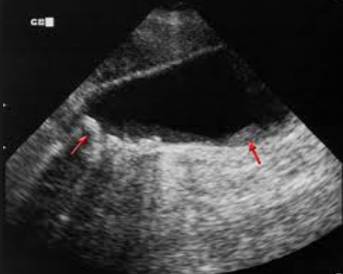

Vì vậy chẩn đoán chủ yếu dựa vào các thăm dò cận lâm sàng. Hiện nay với sự phát triển của các phương tiện chẩn đoán hình ảnh: siêu âm, siêu âm nội soi, chụp cắt lớp vi tính (CT- scanner), chụp cộng hưởng từ hạt nhân (MRI) đã giúp ích rất nhiều cho chẩn đoán polyp túi mật, phân biệt với các hình ảnh khác trong cơ quan gan mật. Trong các thăm dò chẩn đoán phổ biến trên thế giới nêu ở trên thì siêu âm vẫn là phương pháp được lựa chọn chính. Trên siêu âm có thể phát hiện thấy hình ảnh tăng âm bám dính trên bề mặt túi mật, không có bóng cản và không thay đổi theo tư thế người bệnh, đây là dấu hiệu để phân biệt với sỏi túi mật. Mặc dù có độ nhạy và độ đặc hiệu khá cao, nhưng siêu âm không thể phân biệt được là polyp lành tính hay ác tính để có chỉ định điều trị phẫu thuật. Các phương pháp khác cũng được sử dụng như chụp cắt lớp vi tính, siêu âm nội soi nhưng độ đặc hiệu không cao nên còn đang được bàn cãi.